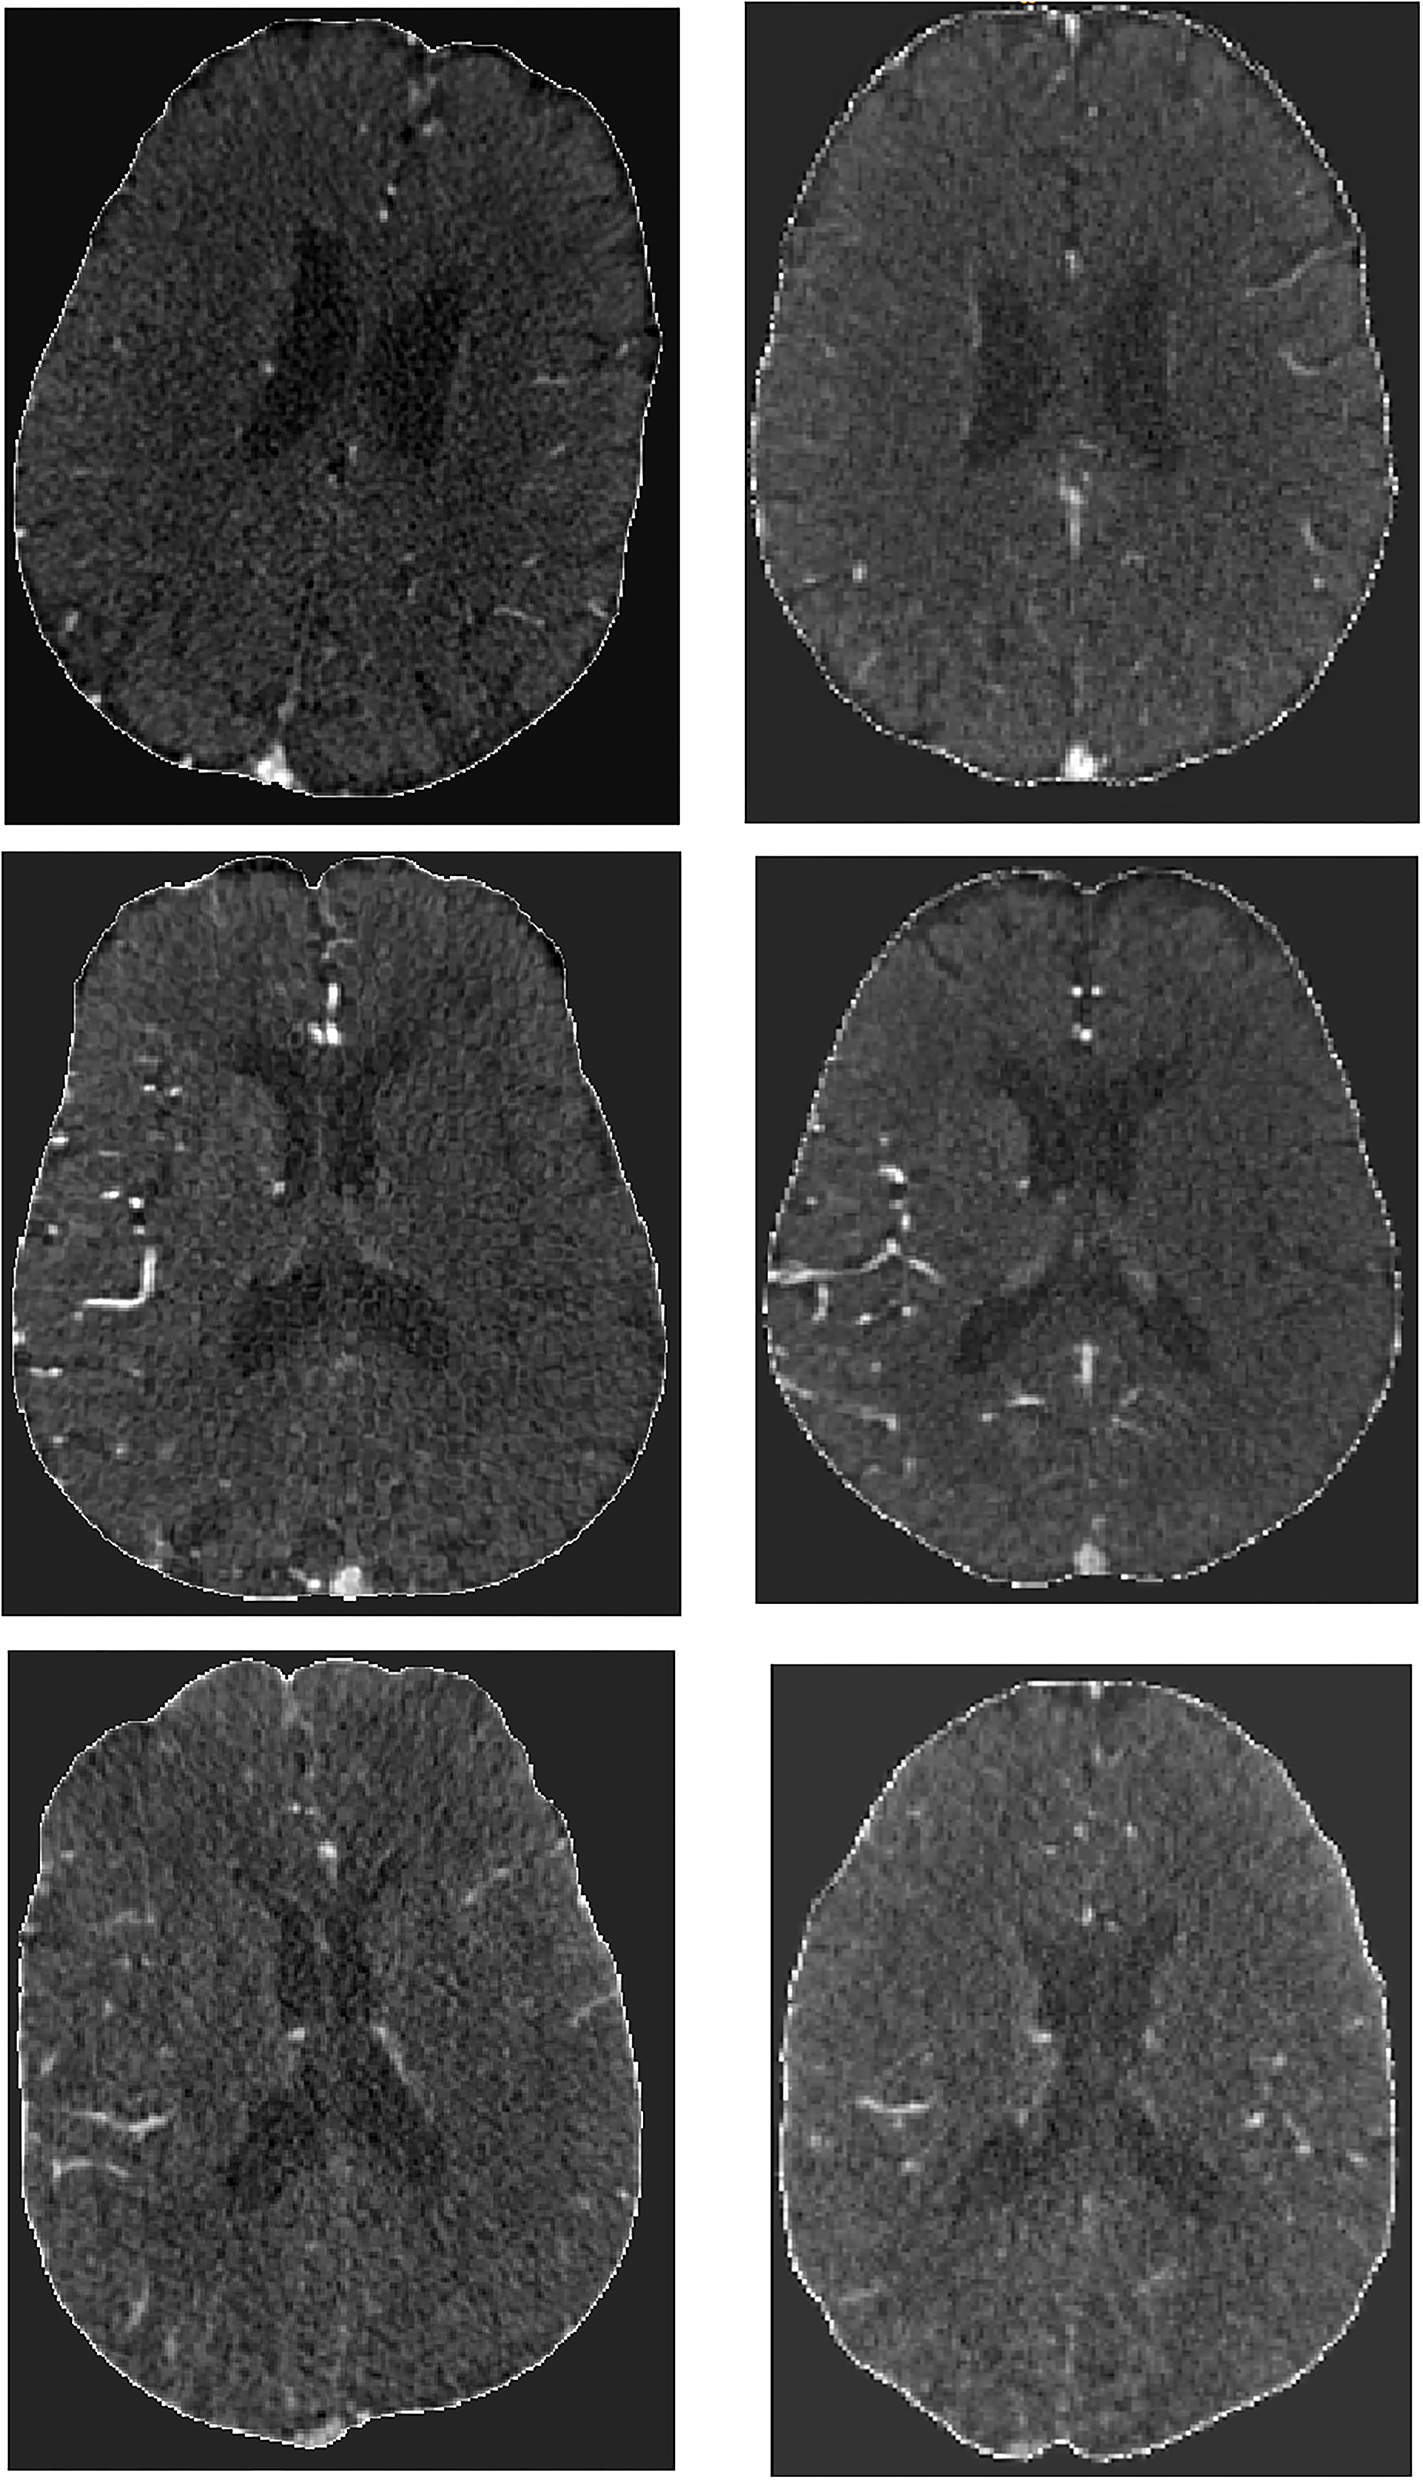

Of 3,279 patients that were eligible for this study, 278 were excluded due to either failure during skull-stripping (133 patients), or because of incomplete scans, severe artifacts or due to failure during image registration (145 patients). In total, 3,001 patients were included, the mean age was 72 years old, and median baseline NIHSS was 16 (Table 1). At 90 days, 1,241 (37%) patients had a good functional outcome (mRS ≤ 2) with 214 missing values (7%). Regarding reperfusion (post-eTICI ≥ 2b), 1,954 (60%) patient had good reperfusion after treatment, with 90 missing values (3%). Figure 2 contains a few examples of skull-stripped scans (on the left) and a few examples of scans that were registered to the atlas (on the right). It is important to highlight that due to registration, the scans no longer have the same slice thickness and number of slices, so there is no one-to-one matching.

Figure 2

Example of skull stripped scans (Left) and post-registration results (Right).